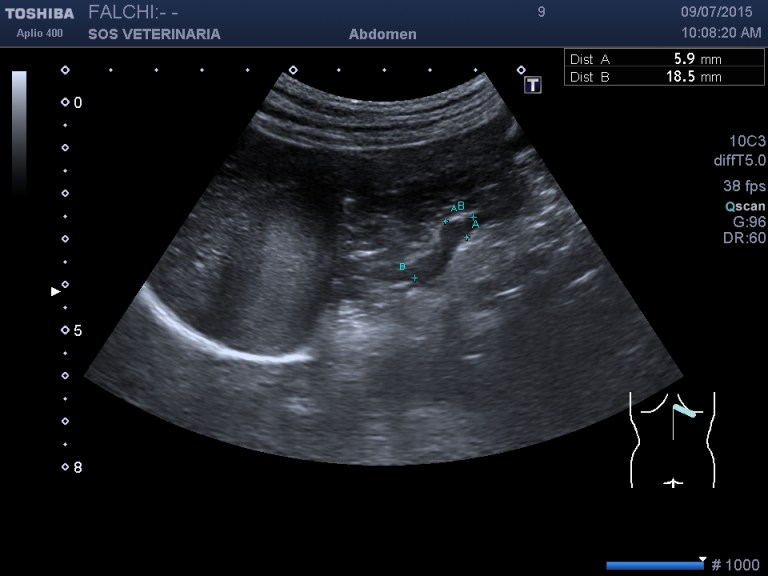

controllo dopo 4 mesi

la lesione e’ cresciuta, il cane sotto somministrazione di vetoryl e’ migliorato nei sintomi dell’ipercorticosurrenalismo ,bene sul piano generale viene visto solo per un controllo

la prima ecografia asse maggiore 3,5 cm

la seconda dopo 2 mesi asse maggiore 4,2 cm